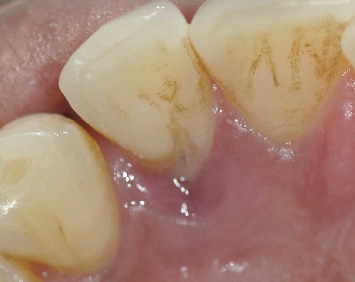

本病例报告讨论了成功处理与III期广泛性C级牙周炎相关的腭深发育沟。尽管先前进行了非手术牙周治疗,但病情进展迅速,需要进一步干预。综合评估显示广泛性牙周炎与局部牙齿相关的易感性因素,由于发育沟在重要的左上侧切牙。最初的非手术治疗包括刮除和根刨(SRP)以及全身抗生素。除发育凹槽部位外,其他部位均有显著改善。手术干预使用腭通道瓣牙成形术和根根成形术来消除剩余的袋和加强菌斑控制。手术成功地解决了问题,在6个月的随访中观察到软组织愈合,残余探探深度为3mm。本病例强调了与腭发育沟相关的挑战,作为牙周炎的局部加重因素。手术技术的使用,如牙成形术和皮瓣访问被证明是有效的管理牙周缺损相关的发育沟,展示了一个成功的结果在这个病人。

This case report discusses the successful management of a deep palatal developmental groove associated with Stage III generalized Grade C periodontitis. Despite prior nonsurgical periodontal therapy, the disease progressed rapidly, necessitating further intervention. A comprehensive evaluation revealed generalized periodontitis with localized tooth-related predisposing factor due to a developmental groove in the vital upper left lateral incisor. The initial nonsurgical treatment involved scaling and root planing (SRP) coupled with systemic antibiotics. Significant improvement was observed, except for the site with the developmental groove. Surgical intervention was performed using a palatal access flap odontoplasty and radiculoplasty to eliminate the remaining pocket and enhance plaque control. The procedure successfully resolved the condition, with soft tissue healing observed at the 6-month follow-up with a residual probing depth of 3 mm. This case highlights the challenges associated with palatal developmental grooves as localized aggravating factors in periodontitis. The use of surgical techniques like odontoplasty and flap access proved effective in managing periodontal defects associated with developmental grooves, showcasing a successful outcome in this patient.